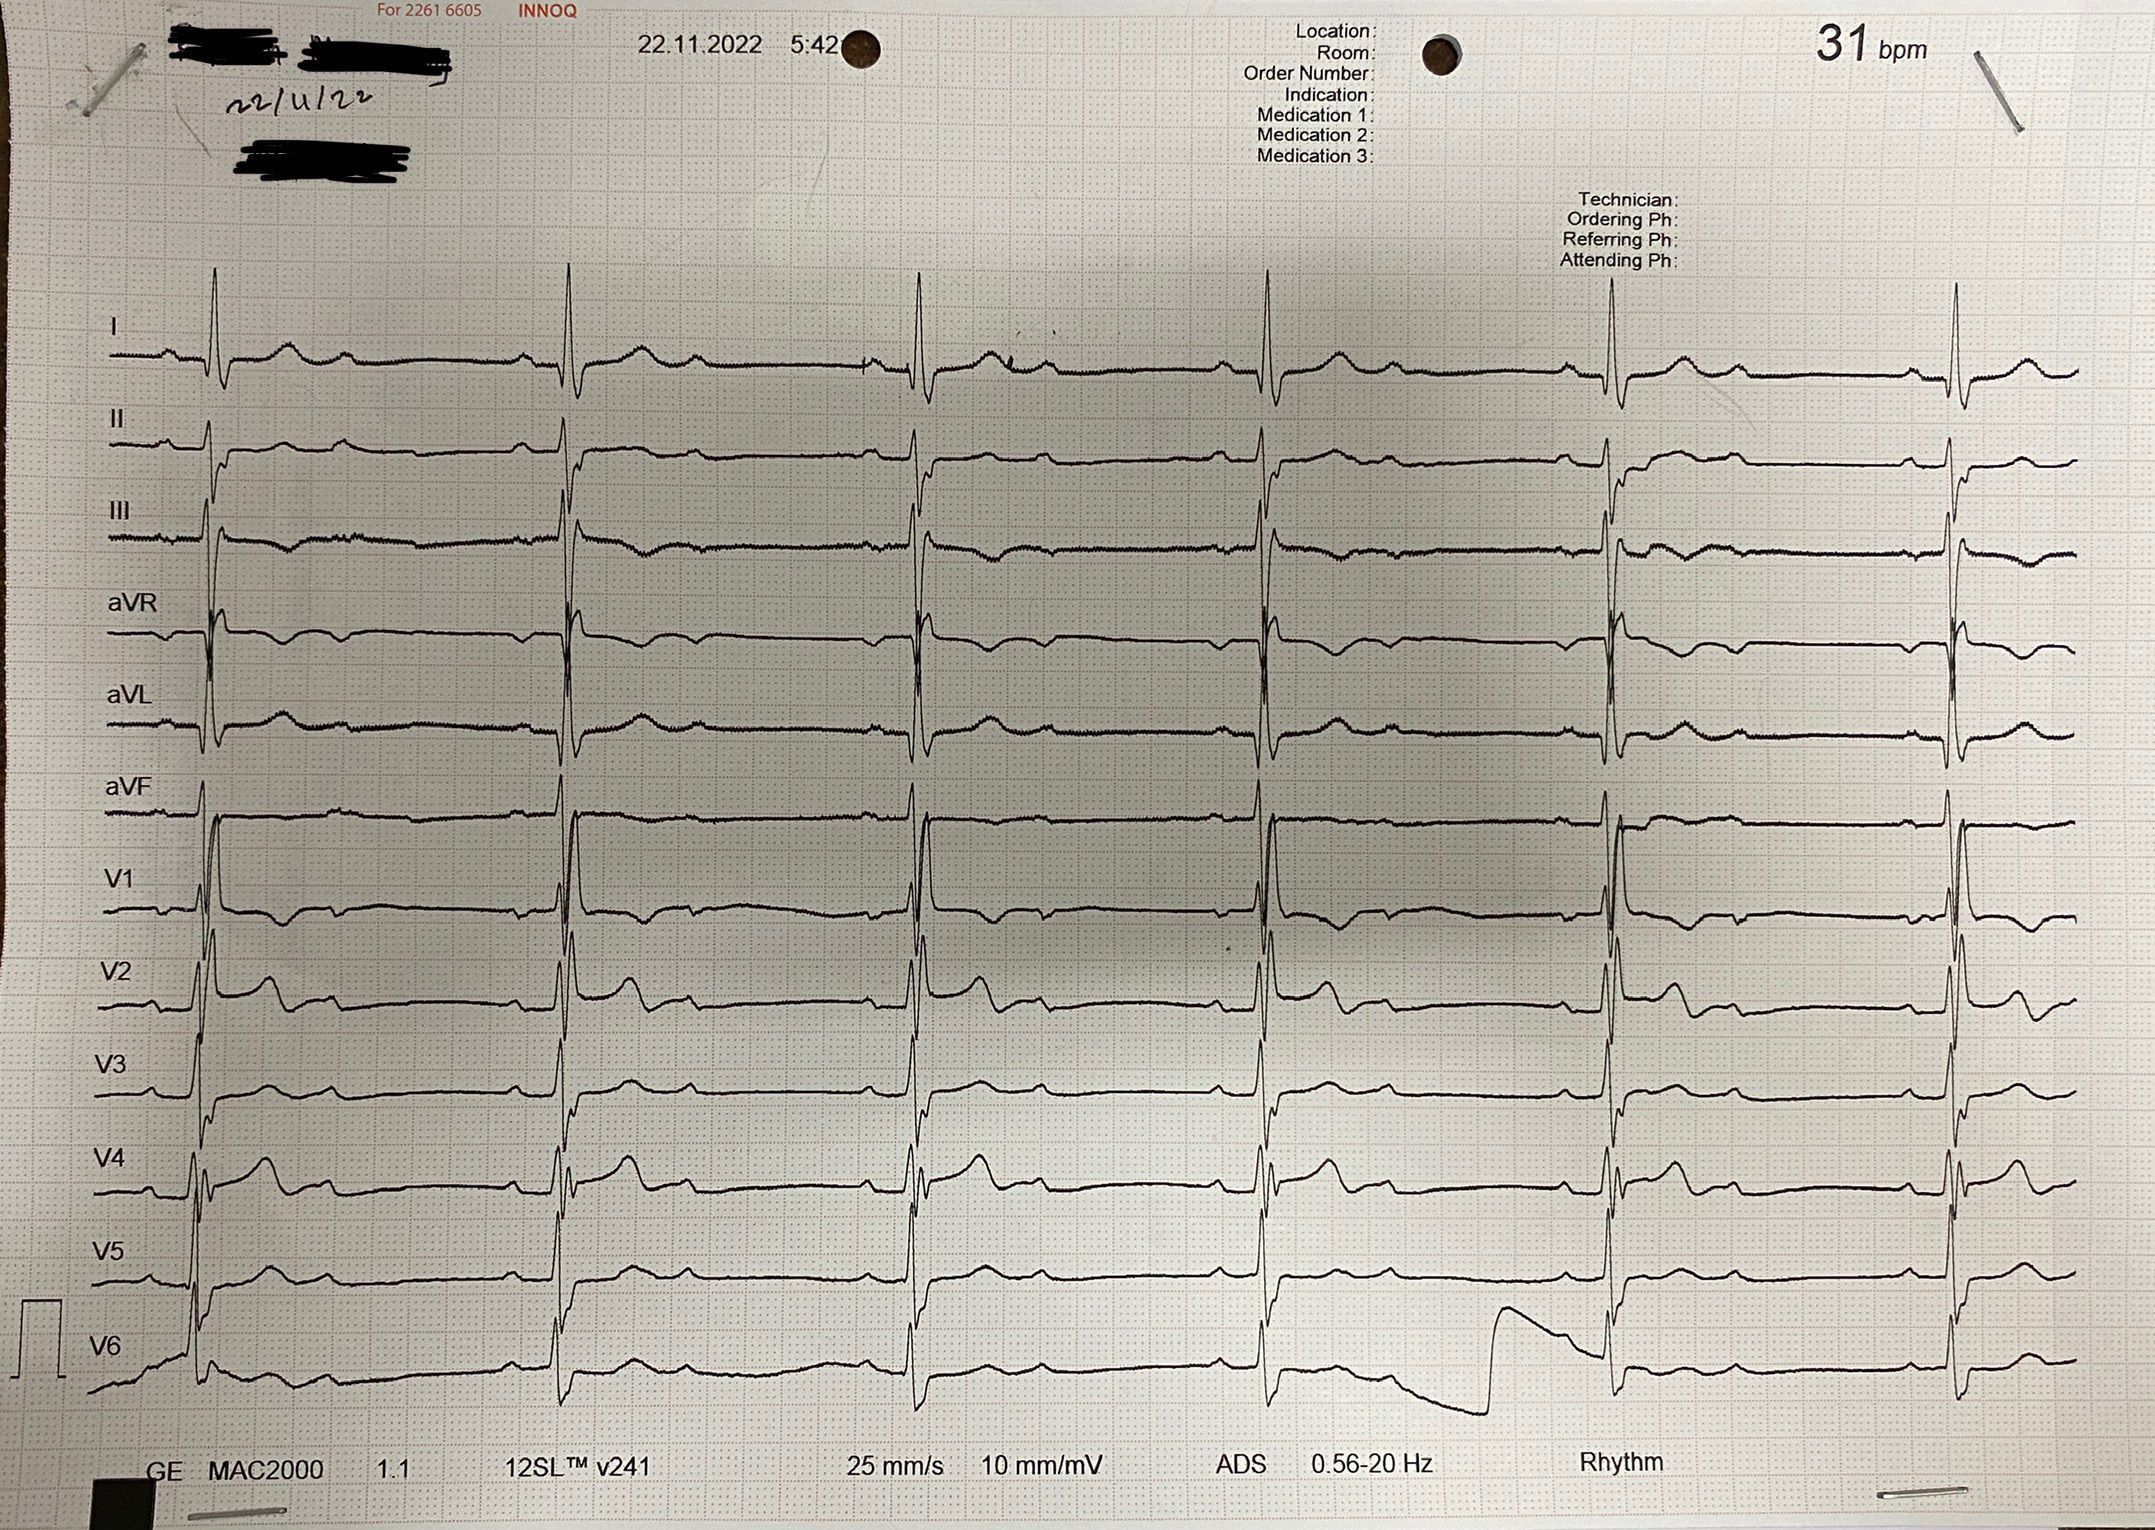

At the first time, i was thinking this is AV block type 1 because as we can see there is prolonged PR-interval and there is no QRS complex that disappear. But when i consult this one to my supervisor, he said that the wave that we cam find after t-wave is not u-wave, it is also p-wave because it has the same mophology with the previous p-wave. And because it has constant prolonged PR-interval and also disappear QRS complex, the rhythm is AV Block type 2 Mobitz 2. What do you think guys?